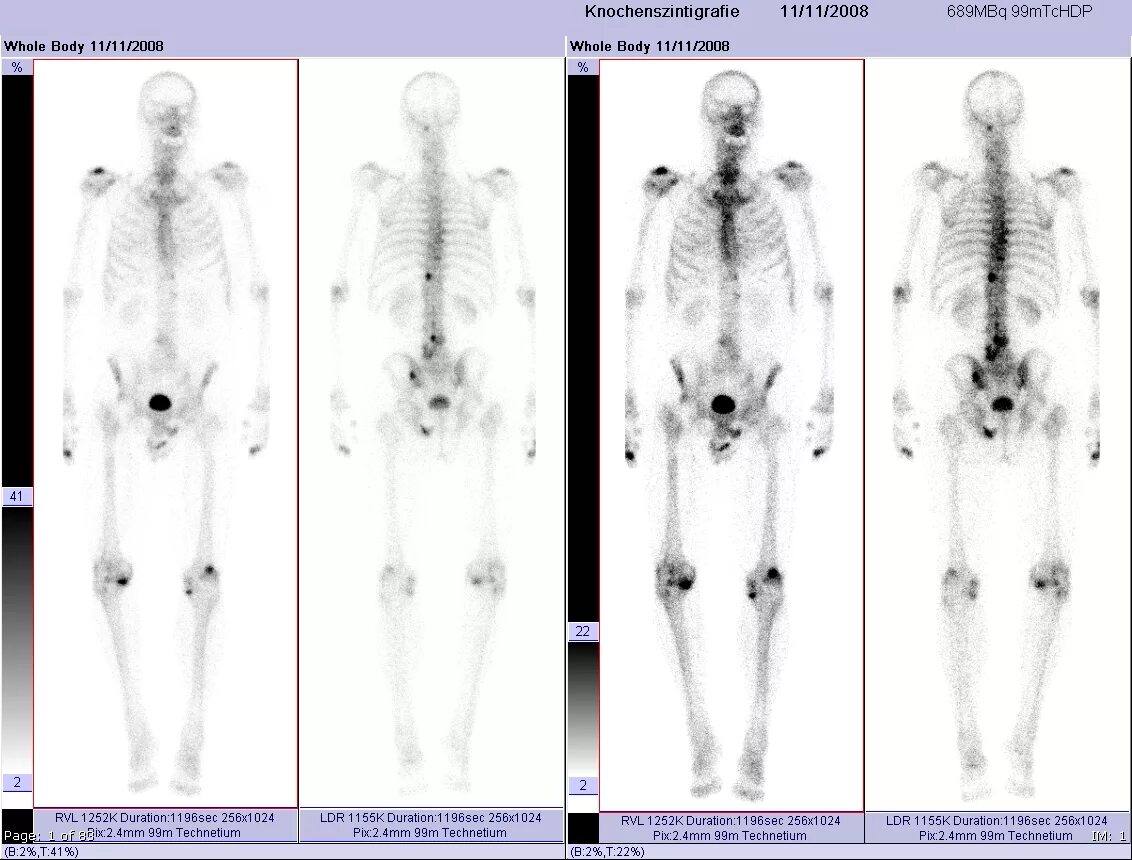

Метастазы скелета